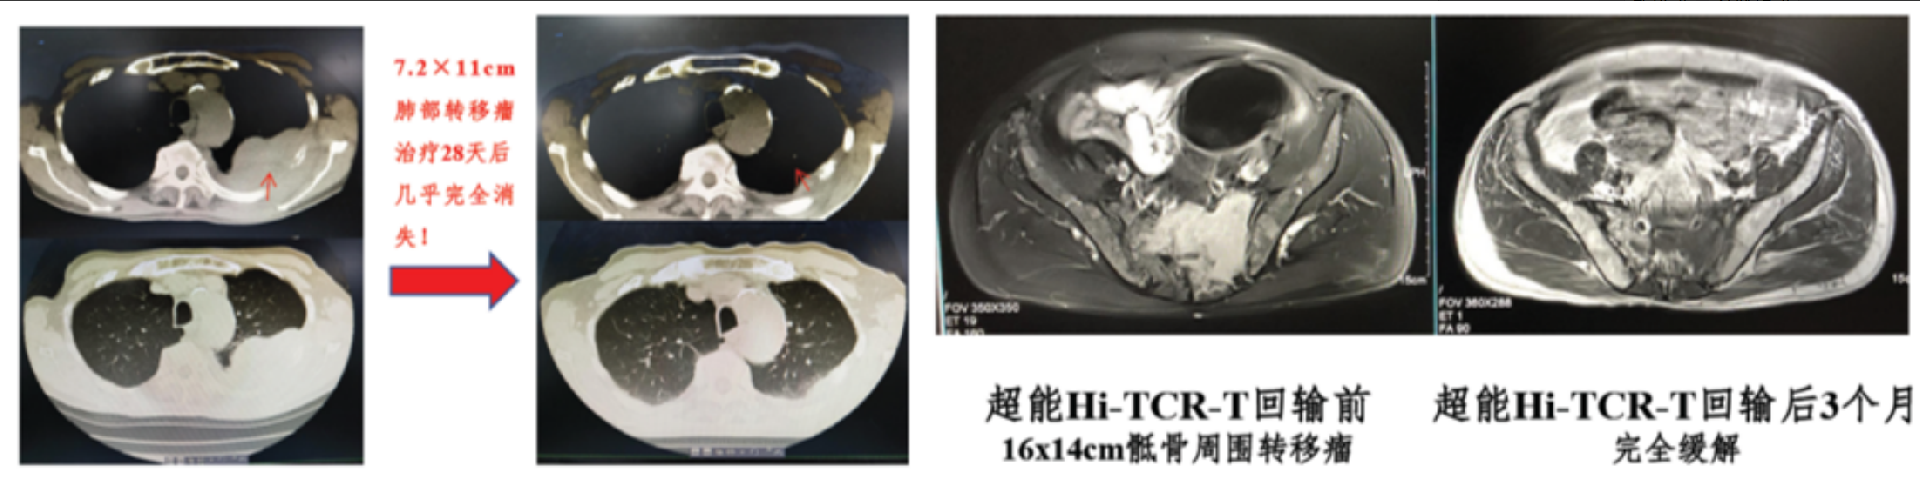

图例:Hi-TCR-T治疗复发/难治性多发性骨髓瘤

临床试验研究证明,Hi-TCR-T治疗初步取得了优异疗效(已治疗10例,完全缓解率100%、且无复发,随访32-66个月)、且安全性极佳(仅伴有发热),总体处于国际领先水平。